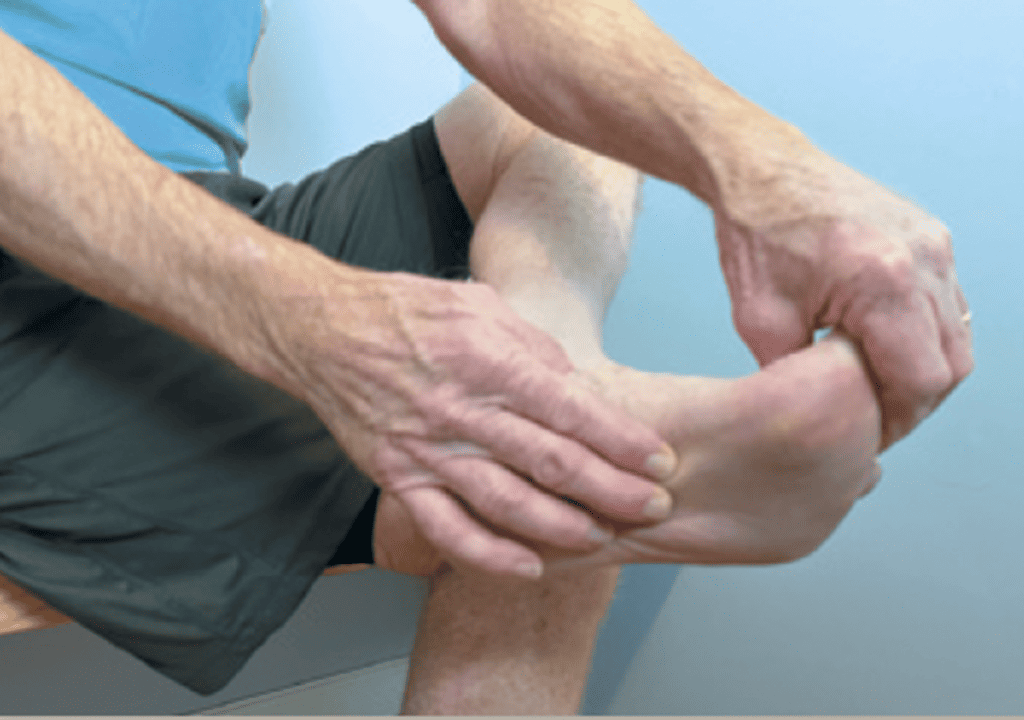

USG Guided plantar fascia injection by Dr Shubha Hegde at Alleviate Pain Clinic

plantar fascia injection by Dr Wiquar Ahmed at Alleviate Pain Clinic, Bengaluru